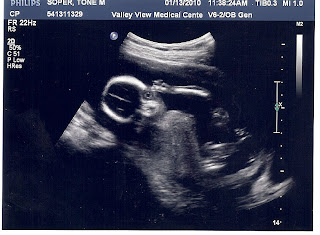

Well everyone... Meet Jack Magnus Soper...

Yeah... I don't even know what to say about this one.. He's just cute already. :)

No... Not the Terminator... It's a baby... Hee hee